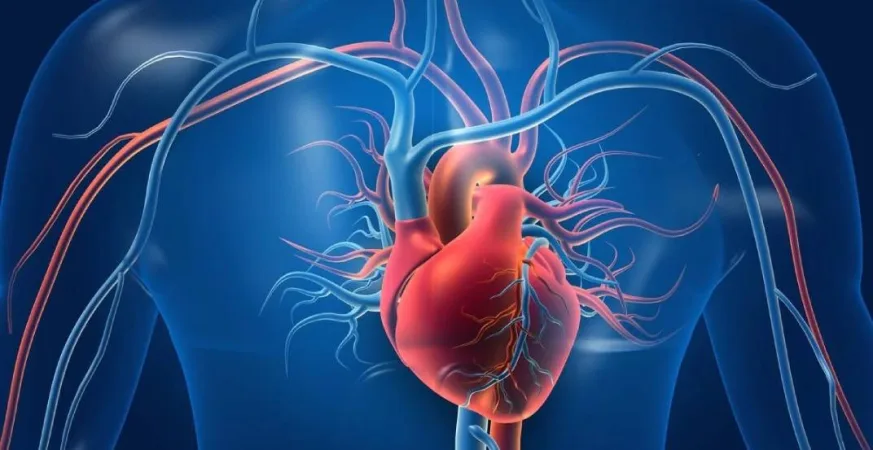

لندن -المملكة المتحدة البريطانية شهد العالم خلال السنوات الأخيرة طفرة غير مسبوقة في ميدان علاج أمراض القلب، حيث باتت الأبحاث الدوائية والتقنيات الطبية الحديثة تفتح آفاقًا جديدة أمام الملايين من المرضى الذين يعانون من مشكلات مزمنة في القلب والأوعية الدموية. ووفق ما أعلنت عنه هيئات طبية عالمية وتقارير بحثية حديثة، فإن عام 2025 يُعد نقطة […]